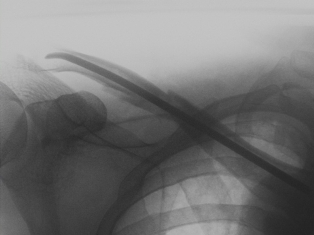

Kompletter Unterarmbruch bei einem 13 jährigen Schüler. Stabilisierung der Speiche und der Elle mit je einem Titanmarkdraht. Die Drähte wurden nach 4 Monaten entfernt.

Kompletter Unterarmbruch bei einem 13 jährigen Schüler. Stabilisierung der Speiche und der Elle mit je einem Titanmarkdraht. Die Drähte wurden nach 4 Monaten entfernt.